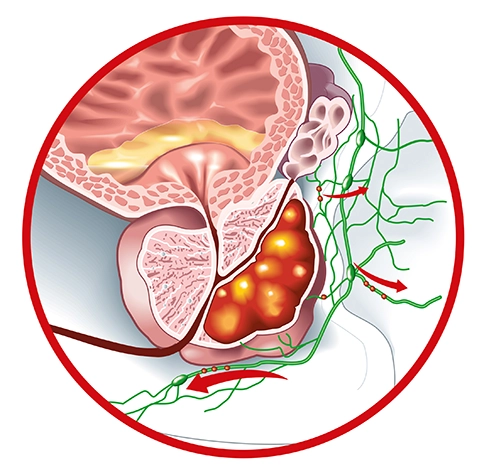

Lycopene+Prostate cancer stands as among the most prevalent cancers and ranks third in causing fatalities among men due to cancer. In the United States, approximately 160,000 new cases of this disease are reported annually, with an estimated prevalence of around 3.3 million

Multiple studies have demonstrated lycopenes anti-cancer properties on prostate cancer cells. These effects are attributed to its ability to hinder cell proliferation, trigger apoptosis, interrupt the cell cycle, and diminish DNA damage.

In summary, lycopene exhibits favorable impacts on the prostate, supported by various mechanisms identified through both laboratory and clinical investigations. -

Nettle Leaf Extract+Research indicates that extracts from nettle root could potentially diminish the proliferation of prostate and cancer cells within the prostate gland. Moreover, they may offer relief from symptoms associated with BPH and regulate the growth of cancerous cells.

In a clinical trial involving 287 BPH patients treated with nettle (Urtica dioica), significant reductions were observed in IPSS (International Prostate Symptom Score), serum PSA (Prostate-Specific Antigen), and prostate size.

The outcomes of this trial revealed that nettle exhibited a superior effect in alleviating clinical symptoms among BPH patients in comparison to a placebo. Various studies employing herbal remedies like nettle have been successful in treating prostate diseases, demonstrating favorable outcomes. Across three clinical trials involving BPH patients, nettle showcased superior efficacy in reducing clinical symptoms compared to a placebo.

Overall, considering its beneficial impact on alleviating BPH symptoms and its safety profile with minimal side effects, nettle is recommended for increased utilization in treating BPH patients. Patients tend to favor it due to its better acceptance and tolerability. -

Boron+Boron is emerging as a targeted inhibitor for prostate cancer cells and their potential spread to other parts of the body. Its unique properties enable it to eliminate these cancerous cells while preserving the health of non-cancerous prostate cells.

Studies have highlighted borons' ability to reduce prostate-specific antigen (PSA), which could aid in preventing or managing the progression of prostate cancer. Additionally, there's evidence suggesting a potential link between boron intake and a decrease in cognitive decline.

Extensive evidence supports the role of boron in mitigating the risks associated with prostate cancer. For instance, one study reported that men with sufficient levels of boron were 64% less likely to develop prostate cancer. Another study in 2001 analyzed the dietary habits of 76 prostate cancer patients and compared them to 7,651 adults without cancer.

According to data from the National Health and Nutrition Examination Survey (NHANES) III, men whose diets provided more than 1.8 mg/d of boron had a 52% lower risk of prostate cancer compared to those whose daily boron intake was less than or equal to 0.9 mg/d.

Potentially Reduce The Risk Of Prostate Cancer:

By reducing the amount of an enzyme that promotes the growth of prostate cancer cells.

Several compounds may reduce inflammation by stopping the production of prostaglandins, which are indicators of inflammation in the body...

...These compounds may also work together to reduce testosterone levels in the prostate.